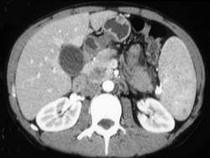

问题 女,56岁,腹部胀痛不适、食欲减退,影像表现如下图,最佳诊断是()

选项 A.急性胰腺炎 B.慢性胰腺炎 C.胰腺腺癌 D.胰腺转移癌 E.胰腺假性囊肿

答案 C